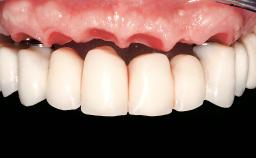

Immediate Loading of Eight Implants in the Maxilla and Six Implants in the Mandible and Final Restoration with Three-Unit and Four-Unit FDPs

Extensive scientific evidence has confirmed that immediately loaded implants with fixed full-arch provisional restorations can osseointegrate with success rates similar to conventionally or delayed loaded implants. A number of immediate-provisionalization techniques for edentulous jaws have been described. Some protocols differ when it comes to prefabricated provisional templates versus complete denture conversion; intrasurgical impressions versus direct relining; and cemented versus screw-retained provisional restorations. In this context, complete-denture conversion has been proposed for either intrasurgical impressions or direct relining. Another possibility is the utilization of a prefabricated provisional to be adapted either in the mouth (by direct relining) or in the laboratory (on a working model obtained from an intrasurgical impression).